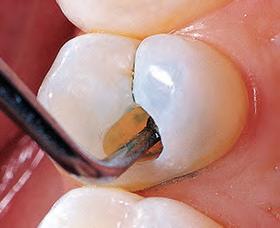

2. Remove old amalgam. Keep caries as a barrier for the time being, in case

DO NOT